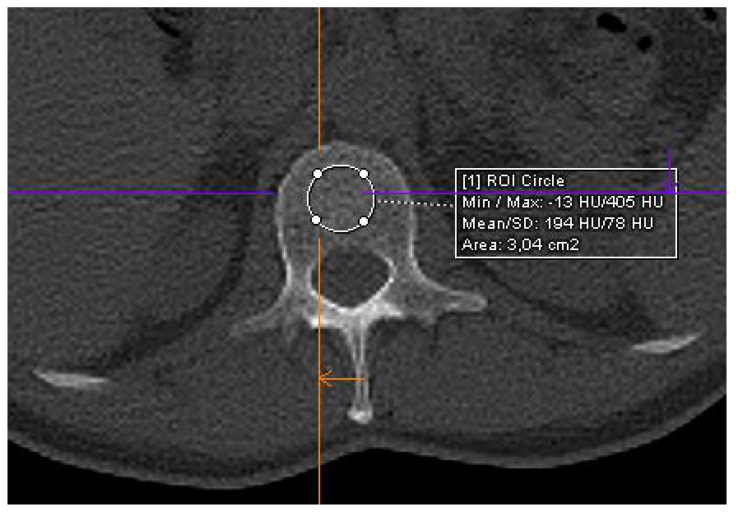

Materials and methods: The study population consisted of 22 patients with MGUS and 51 consecutive patients with newly diagnosed MM (SMM, n = 21; symptomatic MM, n = 36). CT scans were conducted using a 128-slice CT scanner (Somatom go.Top, Siemens, Munich, Germany). Low-dose whole-body CT scans were performed at a single time point for each patient. Trabecular bone density values were obtained by defining regions of interest on non-contrast images at the level of L1 vertebra. A threshold of p = 0.05 was applied to determine statistical significance.

Results: The median Hounsfield unit (HU) value in patients with MGUS, SMM, and MM was 148 HU (range 81-190), 130 HU (range 93-193), and 92 HU (range 26-190), respectively, with a statistically significant difference between the groups (p = 0.0015). Patients with HU values ≤ 92 had lower progression-free survival with statistically significant differences compared to the group with HU values > 92 (p < 0.0499).